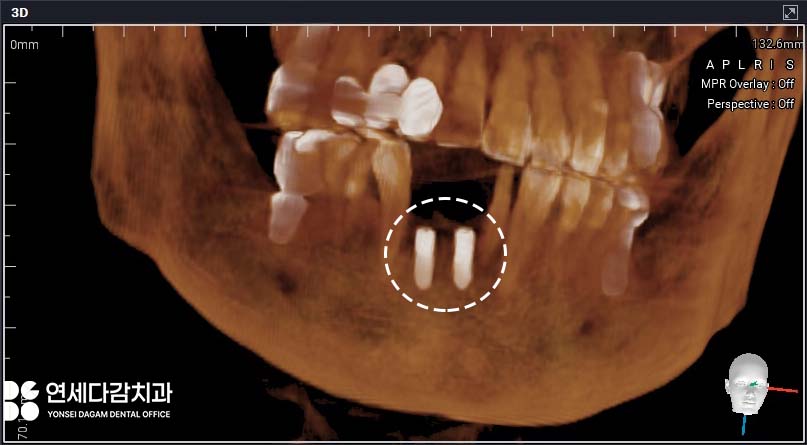

CT 촬영을 통해 평가한

골량과 골질을 토대로

계획한 식립 위치, 각도, 깊이를

고려한 수술이 완료됩니다.

초기 고정 또한

안정적으로 잘 나온 것을 확인한 뒤